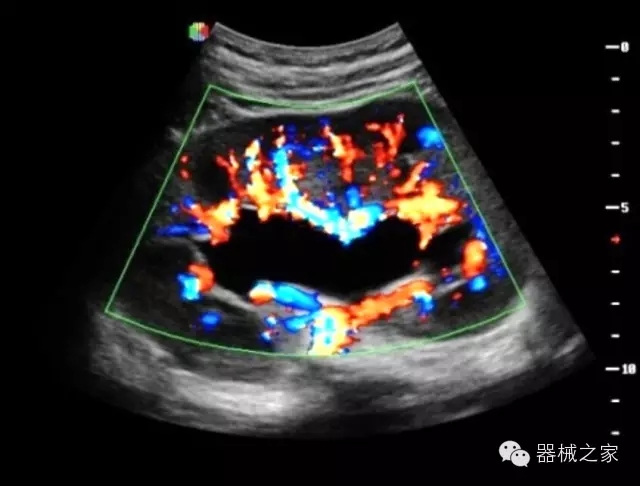

臨床圖片賞析

·全球目前唯一一款配備主機雙探頭接口,整機重量(含電池)在5公斤以內(nèi)的便攜式彩超;

·獨有的HoloTM PW 實時3取樣門PW成像技術,精確進行血管診斷;

·一鍵優(yōu)化B、Color、PW,Auto Doppler自動識別血管位置、偏轉角度等,提高工作效率;

·30°超廣角精細偏轉成像技術,更優(yōu)異的頻譜圖像;